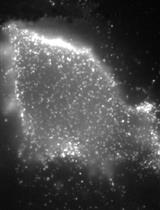

TRIPLE (Insulin, Glucagon and EGFP) Immunofluorescence Staining Protocol in Pancreas

Cover of Nature Cell Biology, featuring study using the protocol.